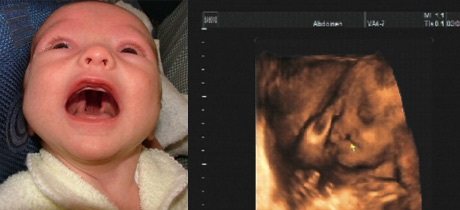

Несмотря на причины возникновения болезни, внешние проявления достаточно типичны. Уже при проведении первого УЗИ будущей маме скажут о наличии и степени выраженности дефекта у малыша. Так что при рождении такого ребенка команда врачей окажет ему всю необходимую помощь.

Диагностика

Адекватная диагностика расщепления неба или губы не представляет большой трудности. Как уже отмечалось, диагноз «волчья пасть» и «заячья губа» становятся очевидными на УЗИ в 1 – 2 триместрах беременности.

В настоящее время диагноз заячья губа и волчья пасть устанавливается еще в утробе матери, по результатам ультразвукового исследования. Формирование челюстей и органов лица происходит в первые 8 недель беременности. Как раз в это время закладываются признаки заячьей губы и волчьей пасти.

Уже на 14-16 неделе можно выявить патологию, но полностью форму и объём поражения врач оценит только после рождения ребёнка. Важно знать, что плод подвижен, он может прикрыть лицо руками или отвернуться к датчику спиной, поэтому узист может не заметить патологический процесс.